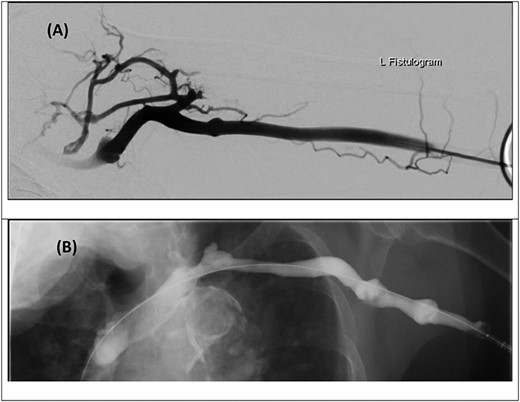

Venous duplex ultrasound of the LUL demonstrating an occlusive thrombus in the left subclavian vein (A), with sluggish flow in the axillary vein (B).

An urgent duplex ultrasound study demonstrated cephalic vein outflow obstruction with occlusive thrombus in the proximal left subclavian/axillary vein confluence (Fig. 1). The basilic vein at the level of the proximal forearm remained patent. He was immediately given a bolus of intravenous unfractionated heparin (UFH) and commenced on a UFH infusion, with a plan for urgent venous thrombectomy.